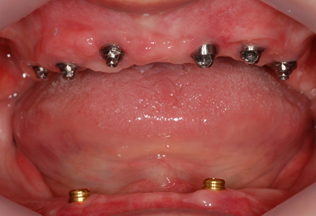

기타 전신질환이 있으신 경우1 기타 전신질환이 있으신 경우2

기존의 틀니는 씹는 힘이 약하고 잇몸이 눌려 통증을 유발할 수 있습니다. 뼛속에 단단히 부착된 임프란트로 자연치아와 같이 씹을 수있고 빼고 넣는 번거로움이 없어집니다.